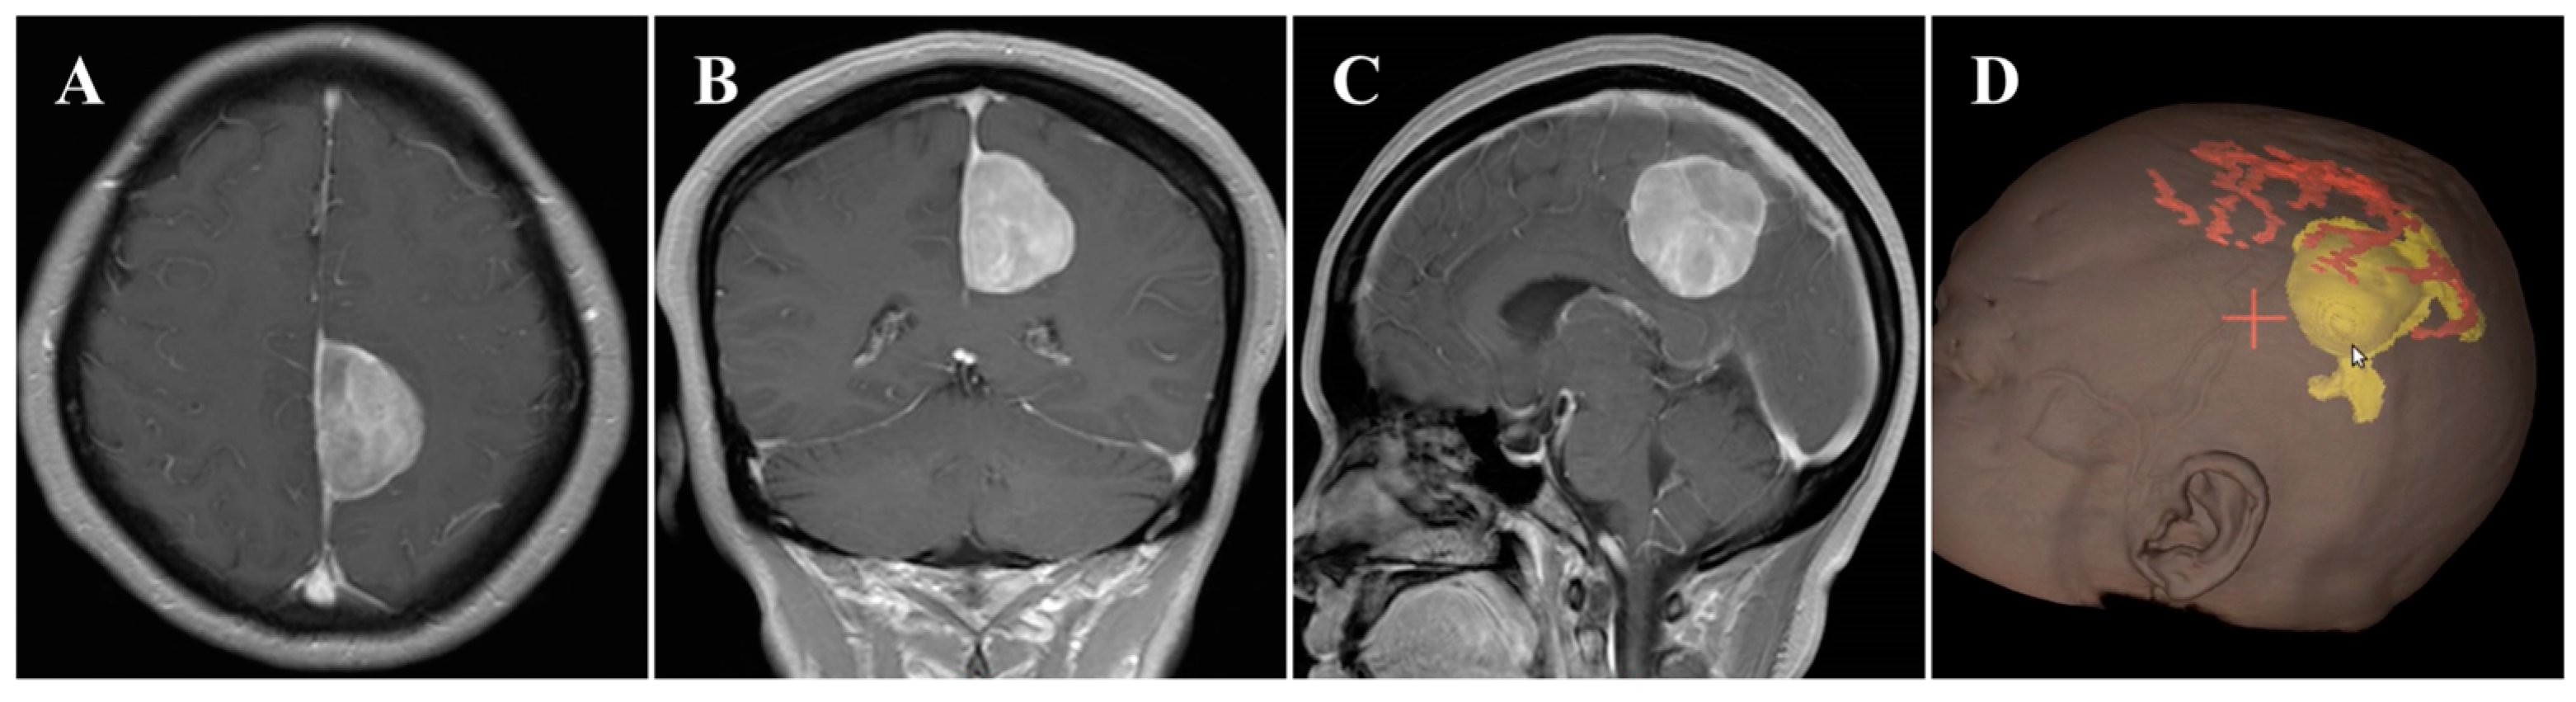

In November 2020, a 55-year-old female was admitted to our hospital and presented with a 6-month history of headache. On general physical examination, she presented with no other remarkable symptoms. MRI revealed a mass approximately 2.9 × 4.2 × 4.1 cm in size, with an attachment in the middle-third of the falx (Figure 1A–C). This parafalcine lesion was mainly extended to the left, with no significant perilesional edema. Neuronavigation showed two drainage veins above the tumor (Figure 1D), which is important for formulating the surgical strategy. Consequently, FM was diagnosed, and surgery was scheduled using the ipsilateral interhemispheric approach to access and remove the tumor using endoscopy through the safe zone between the two veins.

Figure 1.

Preoperative imaging and intraoperative navigation showed a middle-third falcine meningioma. (A–C) Contrast-enhanced MRI axial (A), coronal (B), and sagittal (C) images. (D) Neuronavigation (3D image) demonstrated two drainage veins above the tumor (white arrow).